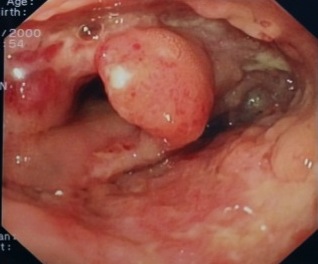

Nel frattempo l’esame endoscopico mostra, a livello di colon e ileo terminale, una mucosa con multiple ulcere, tratti edematosi e iperemici, valvola ileocecale beante, deformata, ulcerata (Figura 3); quadro compatibile con morbo di Crohn. Campioni bioptici vengono inviati in Anatomia patologica e in Microbiologia: flogosi granulomatosa focalmente necrotizzante, colorazione di Ziehl-Neelsen positiva per M. tuberculosis; coltura positiva per M. tuberculosis su biopsia del colon.

Si pone diagnosi di tubercolosi (TB) miliare intestinale e polmonare. Dopo 4 settimane di quadruplice terapia: peso 16 kg, SOF negativo, BAAR e PCR per M. tuberculosis su aspirato gastrico: negativi.